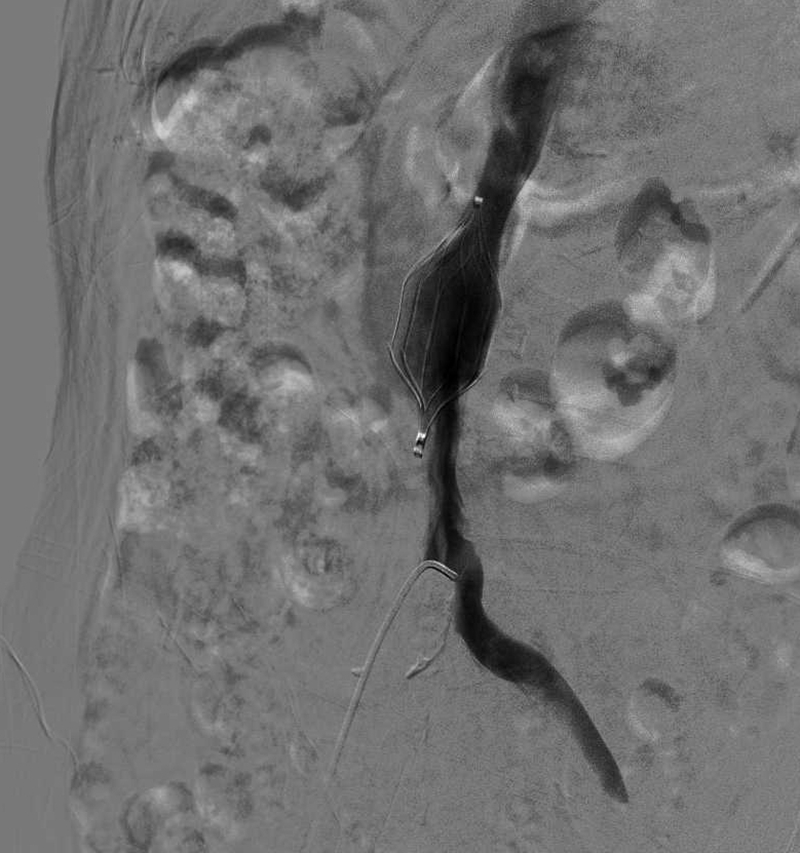

5.主动脉内球囊反搏术(IABP)

IABP手术是治疗低心排综合征的有效手段,是首选的心脏机械辅助方法之一,为心源性休克、顽固性心衰、高危复杂冠脉病变、高危心脏外科手术等患者保驾护航。